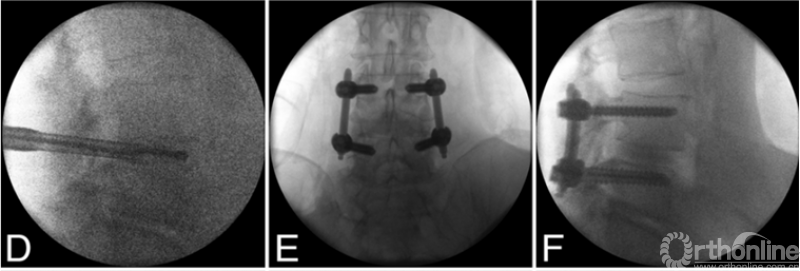

2015年,Morgenstern 报道了改良pTLIF手术治疗椎间盘退行性疾病合并腰椎滑脱(II度以内)的效果。该研究采用了新型的可撑开O型融合器。对比peek椎间融合器以及同型号可撑开的金属O型融合器的治疗效果及融合率,两组之间并没有明显的差异。如图可见,在pTLIF的基础上加用了后路经皮椎弓根固定。平均随访时间为37月,患者ODI/VAS均有明显的改善,该技术对于椎间盘退行性疾病合并腰椎滑脱(II度以内)获得了比较好的治疗及复位效果。

PE-TLIF为经椎间孔入路,使用上关节突导向切除装置定向磨除上关节突,扩大椎间孔区域,在10mm脊柱内窥镜辅助下进行腰椎的减压、椎间植骨及融合器植入,最后辅以经皮置入椎弓根螺钉。